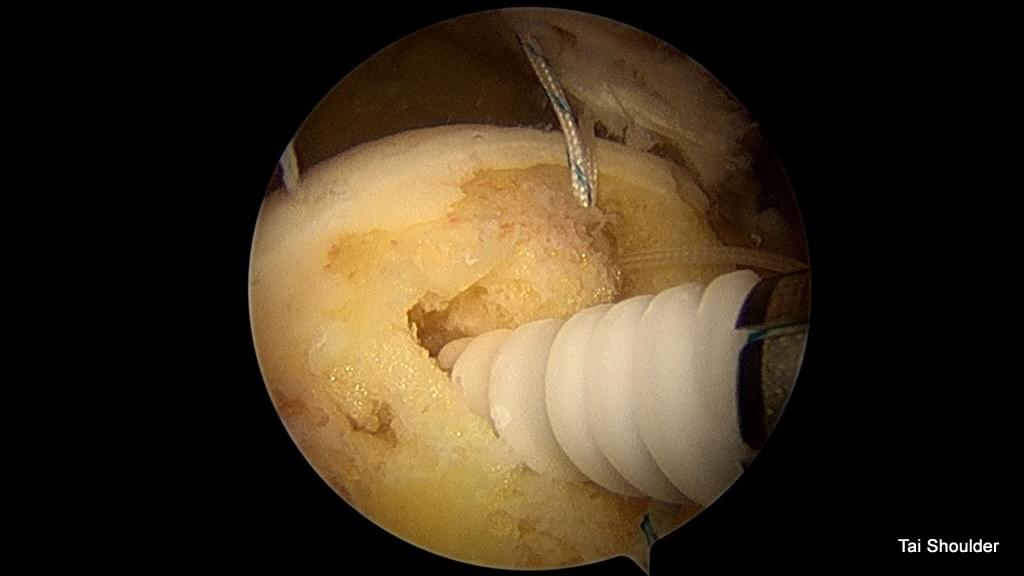

錨釘

旋轉肌破裂,不論小的或是大的整層破裂,均是肌腱從骨頭端斷掉

Knotless SwiveLock® Suture Anchor